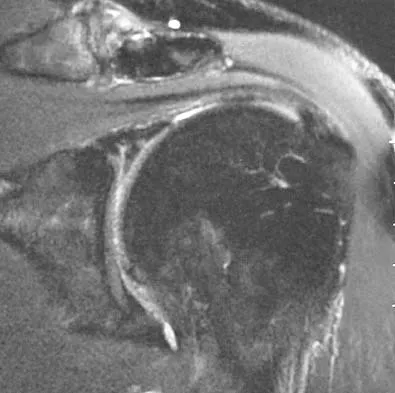

The MRI scan of the shoulder shown in Figure 2 was performed with the arm in abduction and external rotation. The image reveals what condition?

Explanation

Internal impingement of the shoulder is now a well-recognized cause of shoulder pain in the throwing athlete. First described by Walch and associates, it involves contact of the rotator cuff and labrum in the maximally externally rotated and abducted shoulder, such as in the late cocking phase of the throwing motion. Schickendantz and associates have shown this contact to be physiologic in most patients and becoming pathologic with repetitive overhead activity. Schickendantz MS, Ho CP, Keppler L, Shaw BD: MR imaging of the thrower's shoulder: Internal impingement, latissimus dorsi/subscapularis strains, and related injuries. Magn Reson Imaging Clin N Am 1999;7:39-49. Walch G, Boileau P, Noel E, et al: Impingement of the deep surface of the supraspinatus tendon on the posterosuperior glenoid rim: An arthroscopic study. J Shoulder Elbow Surg 1992;1:238-245.